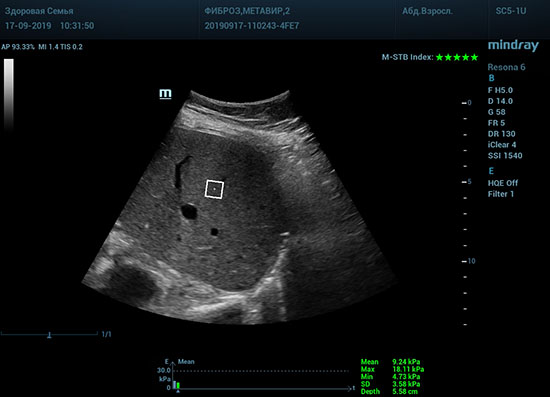

Определение плотности печени. Не ошибся ли оператор при измерении эластических свойств печени? Для оценки критериев качества предусмотрен индекс MBT, который покажет насколько «твердой» была рука оператора и двигалась ли печень. При MBT 5* рука тверда и показатели достоверны. Для оценки качества результатов используется IQR индекс, отображающий колебания показателей в точке измерения при расчете медианы. Показатели при IQR <30% считаются приемлемыми. Техника сканирования через межреберные промежутки требует размещение окна интереса на несколько сантиметром ниже капсулы, для исключения эффекта реверберации. Установка ROI на паренхиму без захвата сосудов, для исключения погрешностей измерения.

Стадия фиброза определяется по системе METAVIR Staging, построенной на данных биопсии и сопоставлении с данными эластографии. Своевременная диагностика фиброза, и начало его лечения, залог благоприятного исхода заболевания.

• METAVIRF0 – норма.

• METAVIRF1 – Портальный фиброз без вовлечения перегородок

• METAVIRF2 – Портальный фиброз с вовлечением нескольких перегородок

• METAVIRF3 – Портальный фиброз с вовлечением множества перегородок

• METAVIRF4 – Цирроз.